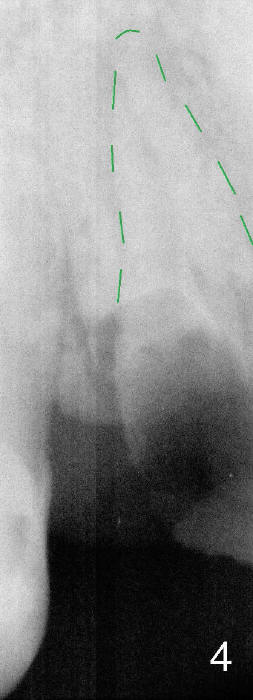

A long implant will be placed (possible 4.5x20 mm, Fig.2). A typical 1st bicuspid has 2 canals. In this case, there are most likely two roots (Fig.3): buccal (Fig.4 green dashed line) and lingual (Fig.5 pink dashed line).